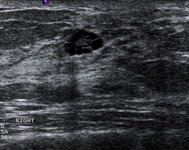

Ultrasonographic image of an invasive carcinoma

Courtesy of Dr Lane Roland, University of Louisville; used with permission